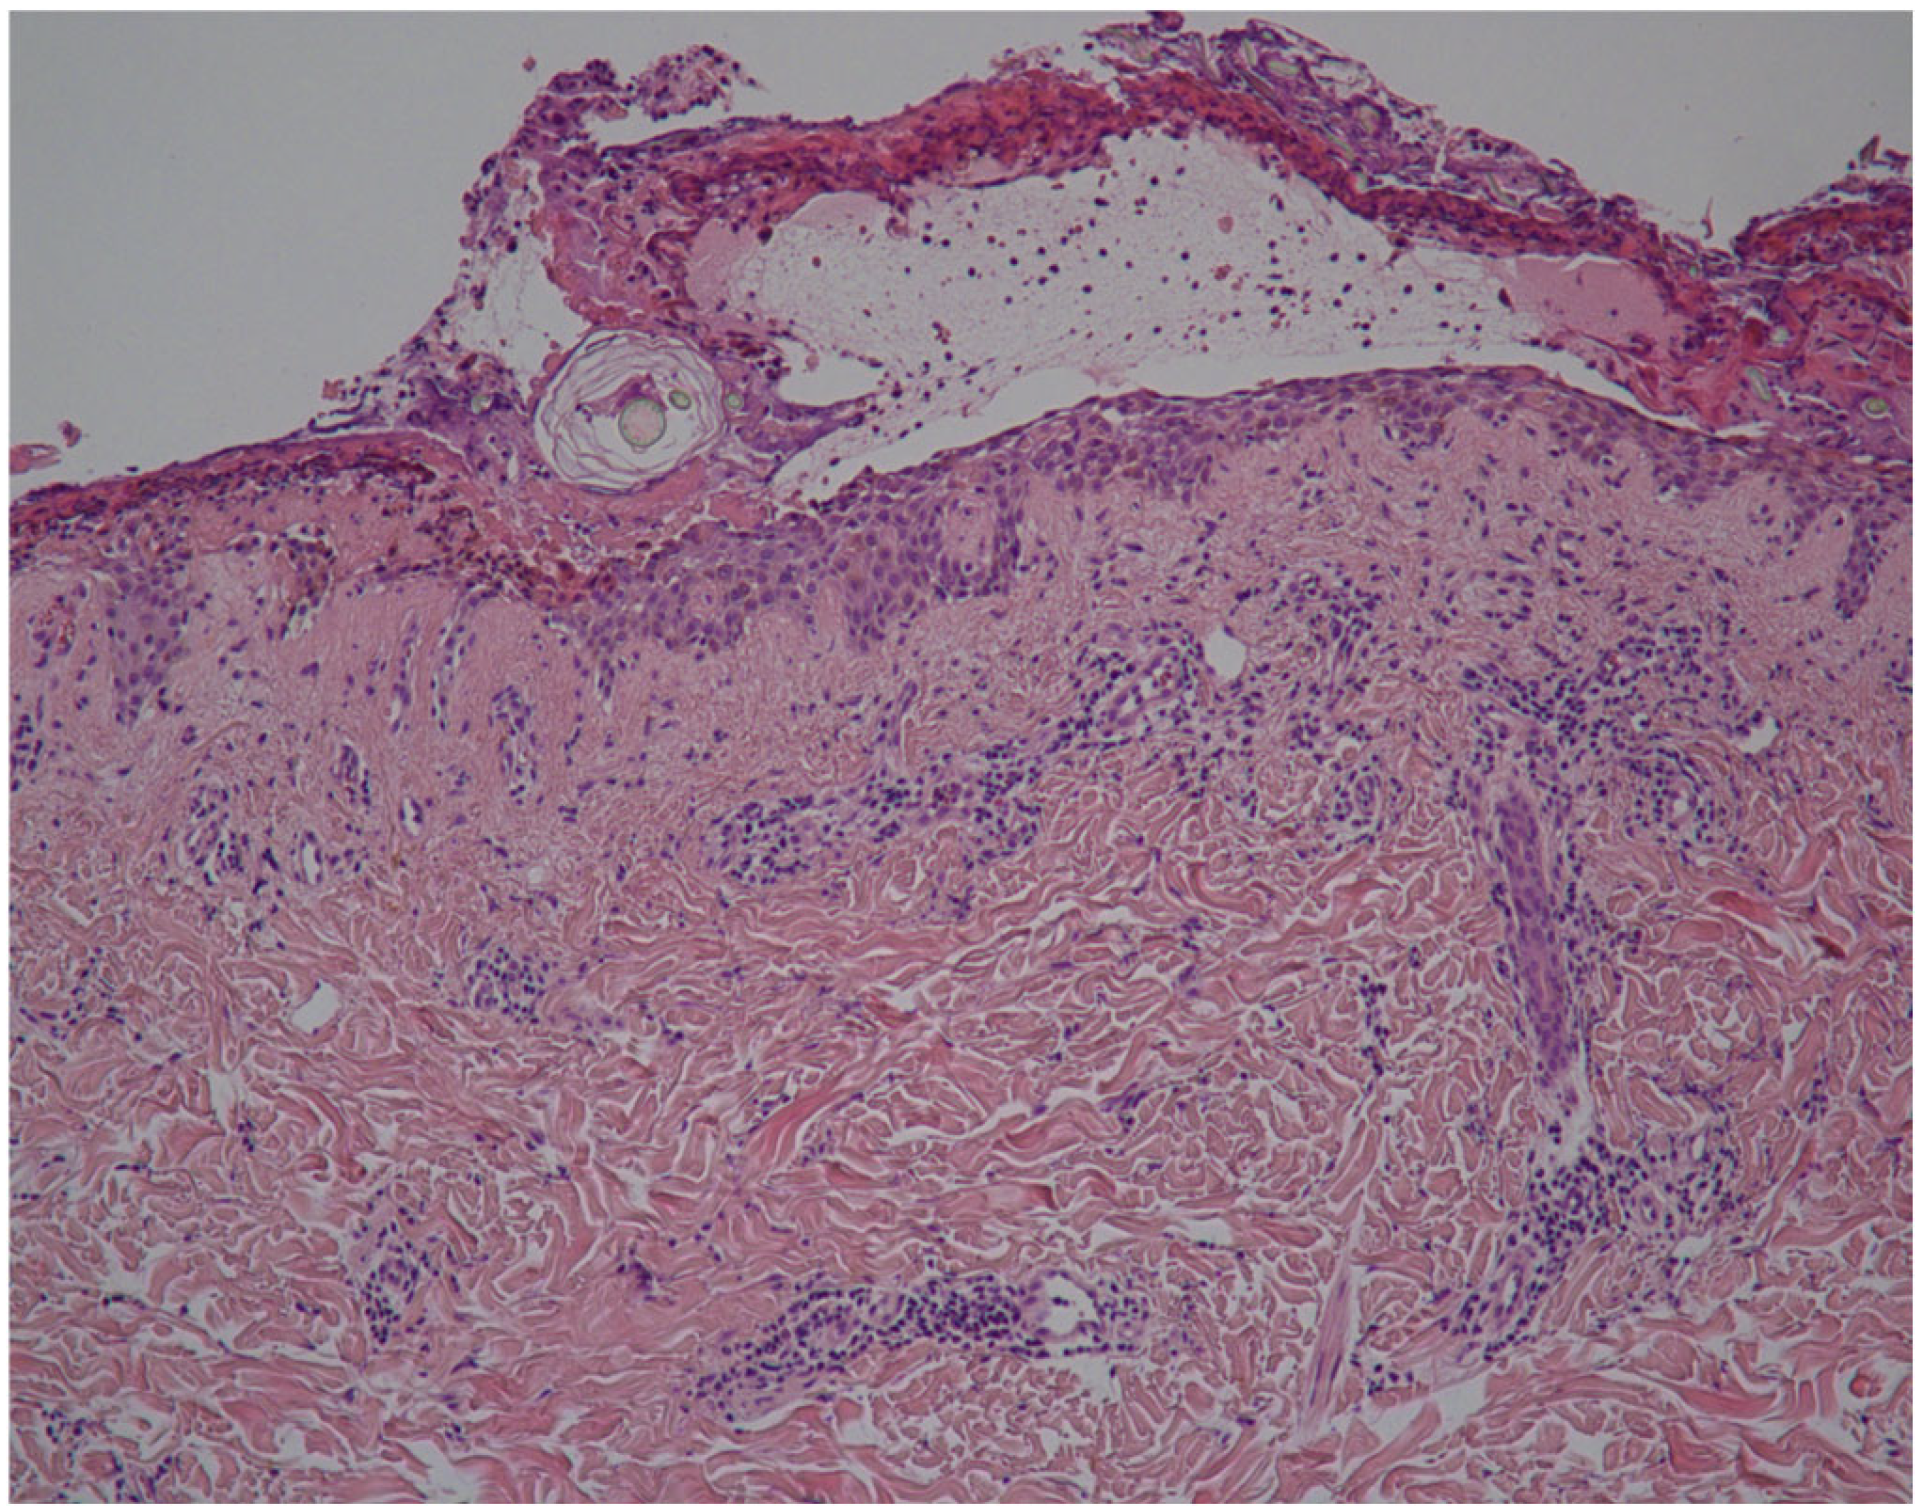

| Cojocaru et al. [2] | Romania | 1 | 34 | F | 2 doses of BNT162b2 | 5 days after 2nd dose | None | Acantholysis at the granular layer (epidermal reticular deposition of IgG and C3, with the absence of IgM, IgA, and fibrinogen | Oral corticosteroid | Complete response after 4 weeks |

| Pham et al. [24] | Vietnam | 2 | 53 | F | Mixed-3 doses of BBIBP-CorV followed by 1 dose of AZD1222 | 3 weeks after 4th AZD1222 dose in the mixed regimen | Amlodipine | Acantholysis above the stratum basalis, dermal lymphocyte, and neutrophil infiltration (intraepidermal IgG and C3) | Corticosteroid and rituximab | Almost complete response in 3 weeks |

| 30 | F | 2 doses of mRNA-1273 | 2 months after 2nd mRNA-1273 dose | None | Acantholysis above the stratum basalis (intraepidermal IgG and C3) | Topical and systemic corticosteroid | Almost complete response in 4 weeks | |||

| Corrá et al. [27] | Italy | 2 | 80 | M | 3 doses of BNT162b2 | 17 days after 3rd dose | Amiloride, hydrochlorothiazide, esomeprazole | Subcorneal acantholysis with neutrophilic infiltration within the blister (PT1: negative; PT2: intercellular IgG deposits) | Oral corticosteroid, rituximab, mycophenolate | Probably good clinical response |

| 66 | F | 2 doses of BNT162b2 | 4 weeks after 2nd dose | Rabeprazole, ticlopidine, atorvastatin, amlodipine, hydrochlorothiazide | Subcorneal acantholysis with neutrophilic infiltration within the blister (PT1: negative; PT2: intercellular IgG deposits) | Oral corticosteroid, rituximab, mycophenolate | Probably good clinical response | |||

| Pourani et al. [25] | Iran | 1 | 75 | M | 3 doses of BBIBP-CorV | 2 weeks after 3rd dose | None | Superficial epidermal bullae, mild spongiosis, superficial dermal perivascular inflammation (intraepidermal IgG and C3) | Topical corticosteroid, rituximab | Significant response in 4 weeks |

| Lua et al. [26] | Singapore | 1 | 83 | M | 2 doses of BNT162b2 | 2 days after 2nd dose | N/A | Subacute spongiotic dermatitis (C3 dermal-epidermal junction and intercellular deposition) | Prednisolone | Good clinical response |

| Hali et al. [28] | Morocco | 1 | 50 | F | 2 doses of BNT162b2 | 15 days after 2nd dose | None | Superficial epidermal blistering process, intact basal layer, intraepidermal eosinophils (intracellular IgG and C3) | Oral corticosteroid | Complete response in 3 weeks |

| Yıldırıcı et al. [29] | Turkey | 1 | 65 | M | 2 doses of BNT162b2 (6 weeks apart) | 1 month after 1st dose; 2 weeks after 2nd dose | Nebivolol, valsartan-hydrochlorothiazide | Intraepidermal acantholytic blister, abundant neutrophils, and scarce eosinophils (intercellular IgG and C3) | Oral corticosteroid, azathioprine | Marked response in 2 weeks |

| Rouatbi et al. [30] | Tunisia | 2 | 70 | M | Mixed-2 doses of CoronaVac followed by 1 dose of BNT162b2 | 7 days after BNT162b2 dose | N/A | Intraepidermal acantholytic blister (intercellular IgG and C3 within the epidermis) | Prednisone, Clobetasol | Good clinical response in 3 weeks |

| 48 | M | 1 dose of AZD1222 | 5 days after 1st dose | None | Superficiel cleft within the epidermis with acantholysis (intercellular IgG and C3 within the epidermis) | Prednisone, Clobetasol | Good clinical response in 2 weeks | |||

| Gui et al. [31] | California | 1 | 67 | F | 2 doses of mRNA-1273 | 2 weeks after 2nd dose | N/A | Intraepidermal acantholysis (intercellular IgG and C3) | Prednisone, Clobetasol and Mupirocin | Almost complete response in 8 weeks |

| Alami et al. [18] | Morocco | 1 | 44 | M | 2 doses of BBIBP-CorV | 7 days after 1st dose | None | Acantholysis with superficial intra-epidermal cleavage (intercellular IgG) | Prednisone, Azathioprine | No good clinical response |

| Reis et al. [32] | Portugal | 1 | 35 | F | 2 doses of BNT162b2 (6 weeks apart) | 2 weeks after 2nd dose | None | Acantholitic keratinocytes and detachment of the stratum corneum (intercellular deposition of IgG and C3) | Prednisolone, Clobetasol | Good clinical response in 4 weeks |